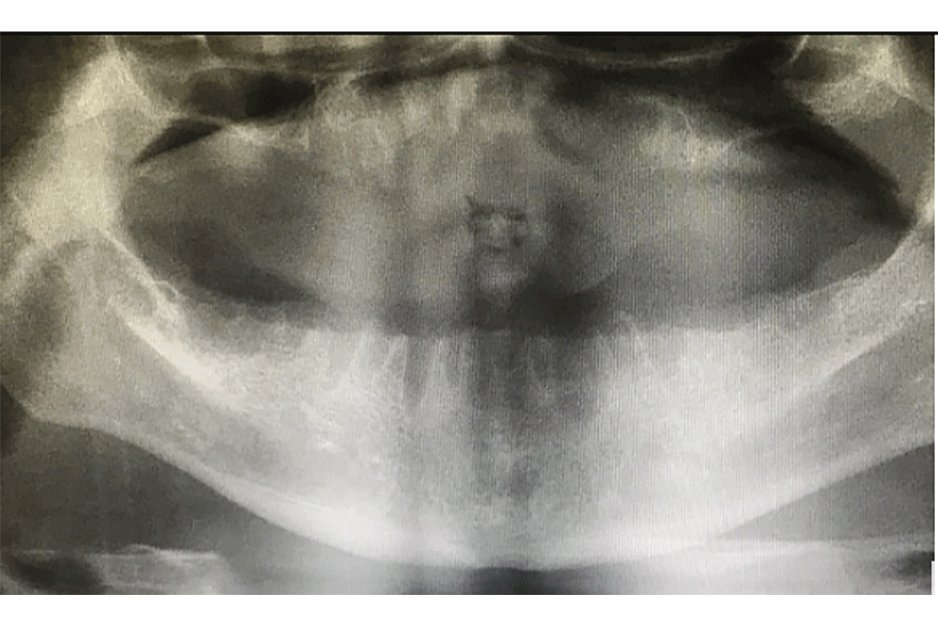

A patient visited Dr. Rodriguez’s dental office in Caracas, Venezuela, with a severe periodontal problem. He had had multiple extractions due to problems with dental mobility, periodontitis and large cavities. The patient and Dr. Richard decided to proceed with the remaining extractions and place implants on the superior and inferior maxillaries.

The patient began his treatment with the placement of eight implants. The process of cicatrization and osseointegration of the implants took four months.

After the placement of impression copings and pick-up copings, Dr. Rodriguez used silicon for the impression of both maxillaries. According to the design, the proper abutments were chosen for a correct insertion of the prosthetics, giving the patient a balanced occlusal load for correct chewing function.